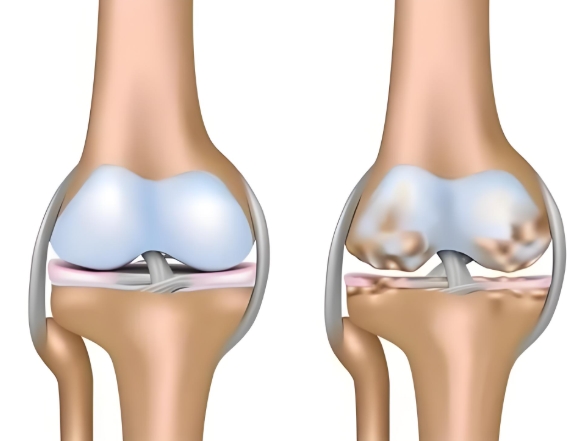

鹽酸和硫酸氨基葡萄糖膠囊都是氨基葡萄糖類(lèi)藥物,能為關(guān)節(jié)軟骨提供合成原料,在促進(jìn)軟骨基質(zhì)的修復(fù)與再生的基礎(chǔ)上,補(bǔ)充關(guān)節(jié)滑液以減少摩擦,同時(shí)通過(guò)抑制關(guān)節(jié)腔內(nèi)的炎癥因子,從多個(gè)方面幫助延緩骨關(guān)節(jié)炎的進(jìn)展[1],但它們?cè)谂R床療效上卻存在一定差異。

根據(jù)國(guó)際醫(yī)學(xué)四大期刊之一《美國(guó)醫(yī)學(xué)會(huì)雜志》上發(fā)布的一項(xiàng)研究表明,硫酸氨基葡萄糖在緩解膝骨關(guān)節(jié)炎疼痛、改善關(guān)節(jié)活動(dòng)功能方面,效果優(yōu)于鹽酸氨糖等33種骨關(guān)節(jié)炎常用藥[2]。還有相關(guān)研究顯示,硫酸氨基葡萄糖不僅能延緩關(guān)節(jié)間隙變窄,還能從根源改善關(guān)節(jié)結(jié)構(gòu)、減緩磨損。而鹽酸氨基葡萄糖在這一關(guān)鍵指標(biāo)上的效果尚未明確。因此,在關(guān)節(jié)保護(hù)的“確切性”上,硫酸氨基葡萄糖顯然更具優(yōu)勢(shì)。

硫酸氨基葡萄糖膠囊中含有的硫酸根是人體關(guān)節(jié)軟骨中蛋白聚糖的天然組成成分。這種與人體兼容的“內(nèi)源性”特質(zhì),讓它口服后吸收利用率可達(dá)90%[3]。而且對(duì)胃腸道會(huì)更溫和,耐受性更佳。反觀鹽酸氨基葡萄糖膠囊,它所含的氯離子不是關(guān)節(jié)正常代謝所需,可能會(huì)在口服后刺激胃腸道黏膜[4]。這種刺激不僅會(huì)引起腸道不適,還會(huì)干擾藥物在腸道的吸收,降低其生物利用度。